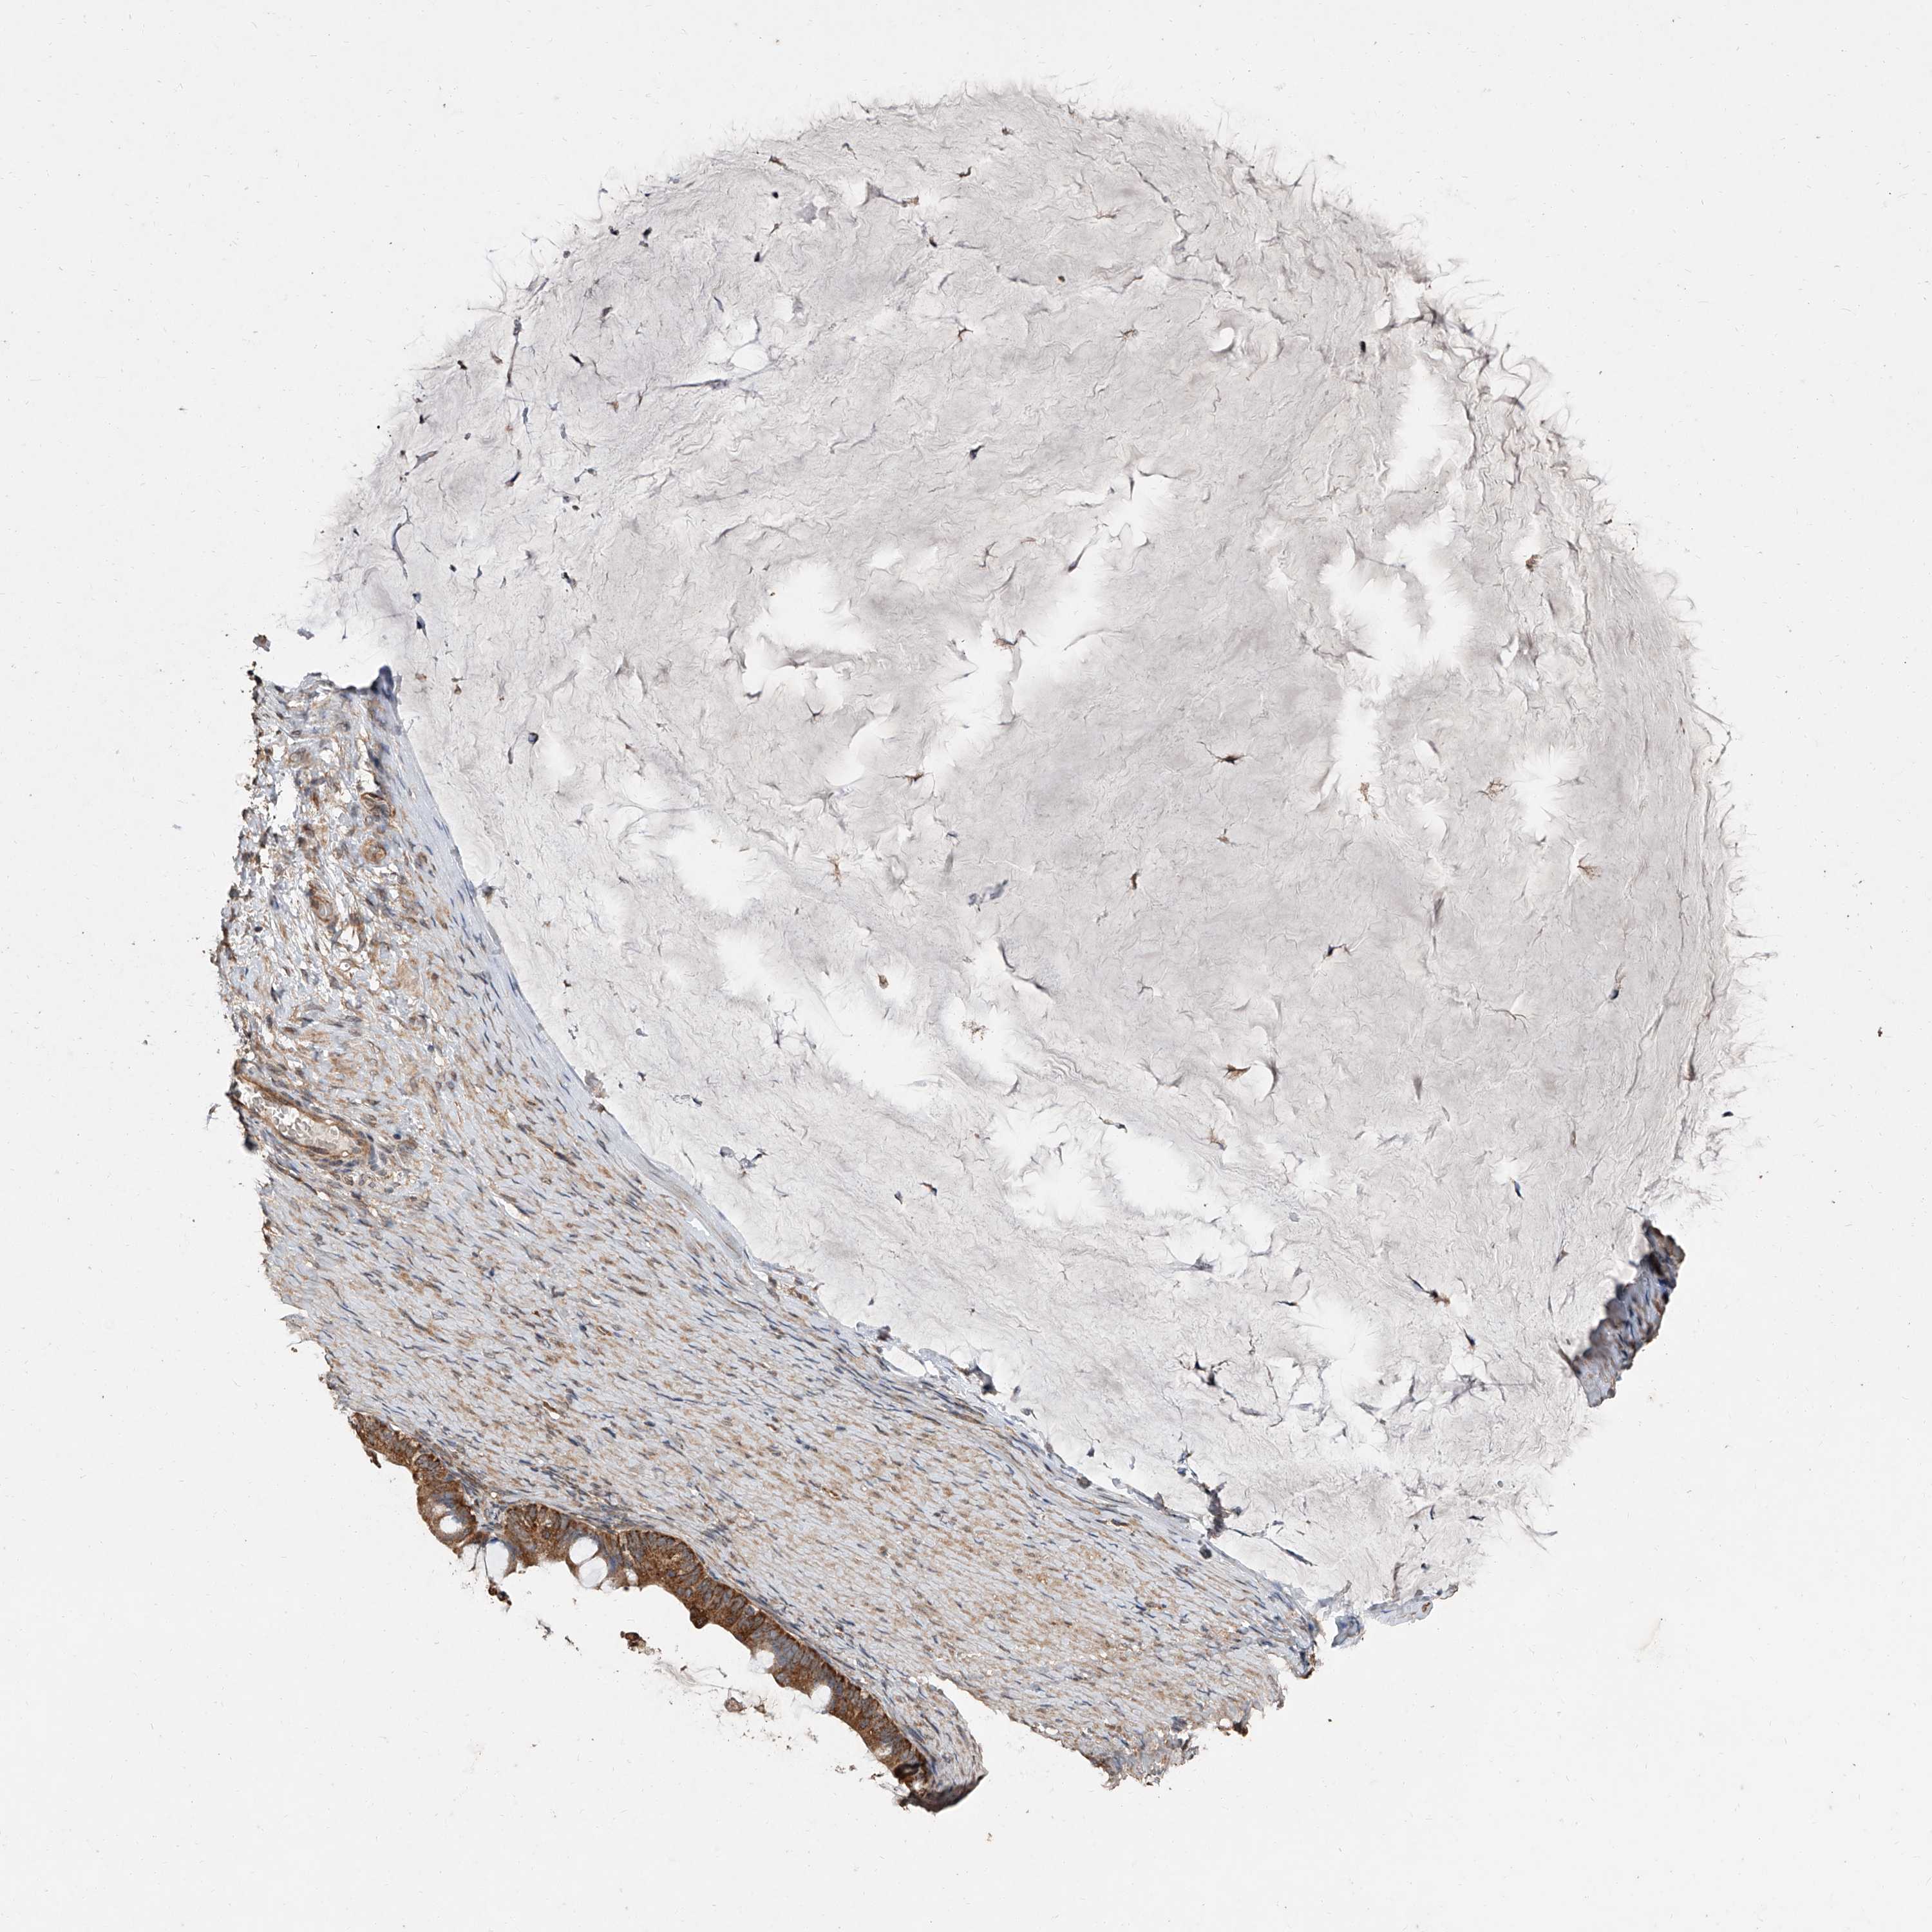

OVARIAN CANCER - Protein expressioni

A mouse-over function shows sample information and annotation data. Click on an image to view it in a full screen mode. Samples can be filtered based on level of antibody staining by selecting one or several of the following categories: high, medium, low and not detected. The assay and annotation is described here.

Note that samples used for immunohistochemistry by the Human Protein Atlas do not correspond to samples in the TCGA dataset.

Antibody stainingi

Antibody staining in the annotated cell types in the current human tissue is reported as not detected, low, medium, or high, based on conventional immunohistochemistry profiling in selected tissues. This score is based on the combination of the staining intensity and fraction of stained cells.

Each image is clickable and will lead to virtual microscopy that enables deeper exploration of all samples and also displays staining intensity scores, fraction scores and subcellular localization as well as patient and tissue information for each sample.

Antibody HPA030159

Antibody HPA030160

Antibody HPA030161

Cystadenocarcinoma, mucinous, NOS